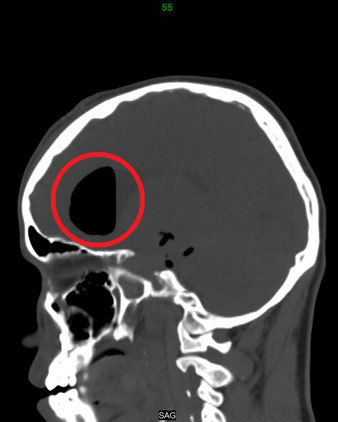

وأوضح الدكتور ماجد قلادة استشاري جراحة العمود الفقري والمخ والأعصاب، أن المريض تم تحويله من مستشفى آخر بعد محاولة علاجه بإجراء عمليتين ولكن دون جدوى. مشيرًا إلى أنه تم إخضاع المريض للفحوصات المخبرية والرنين المغناطيسي (M.R.I) والتصوير المقطعي (C.T. Scan) التي حددت بدقة أماكن الكسور المتهشمة.

وعن كيفية إصلاح كسور الجمجمة، أوضح الدكتور قلادة أنه بعد دراسة الملف الصحي للمريض تم وضع برنامج علاجي للمريض على مرحلتين، مشيرًا لى أن المرحلة الأولى شهدت إجراء عملية جراحية استغرقت 7 ساعات، تم فيها فتح الجمجمة من أعلى والاستعانة بجزء صغير من عضلة المضغ بالفم لإصلاح الغطاء الخارجي للمخ ومعالجة الكسور.

من جهته بين الدكتور هشام توفيق استشاري الأنف والأذن والحنجرة وجراحات المناظير، أن المرحلة الثانية من العلاج كانت مهمة للغاية، موضحًا أنها عملت على منع تسرب سائل النخاع الشوكي (CSF Leak) من فتحة الأنف والحيلولة دون حدوث أعراض جانبية خطيرة، قد تترتب عن ذلك التي قد تؤدي إلى إصابة المريض بالتهاب سحائي، لافتًا إلى أن الجراحة تم تنفيذها بعد يومين من العملية الأولى، حيث استمرت أكثر من 4 ساعات باستخدام منظار الجيوب الأنفية المتطور الذي يتيح إمكانية ترقيع الفراغات الناتجة عن كسر عظمة الجيب الأنفى الخلفي بقاع الجمجمة «Sphenoid Sinus» علاوة على إصلاح جزء آخر بالجيب الأنفى العلوي «Ethmoid Sinus» وذلك بالاستعانة برقعات صناعية «Allo Graft».